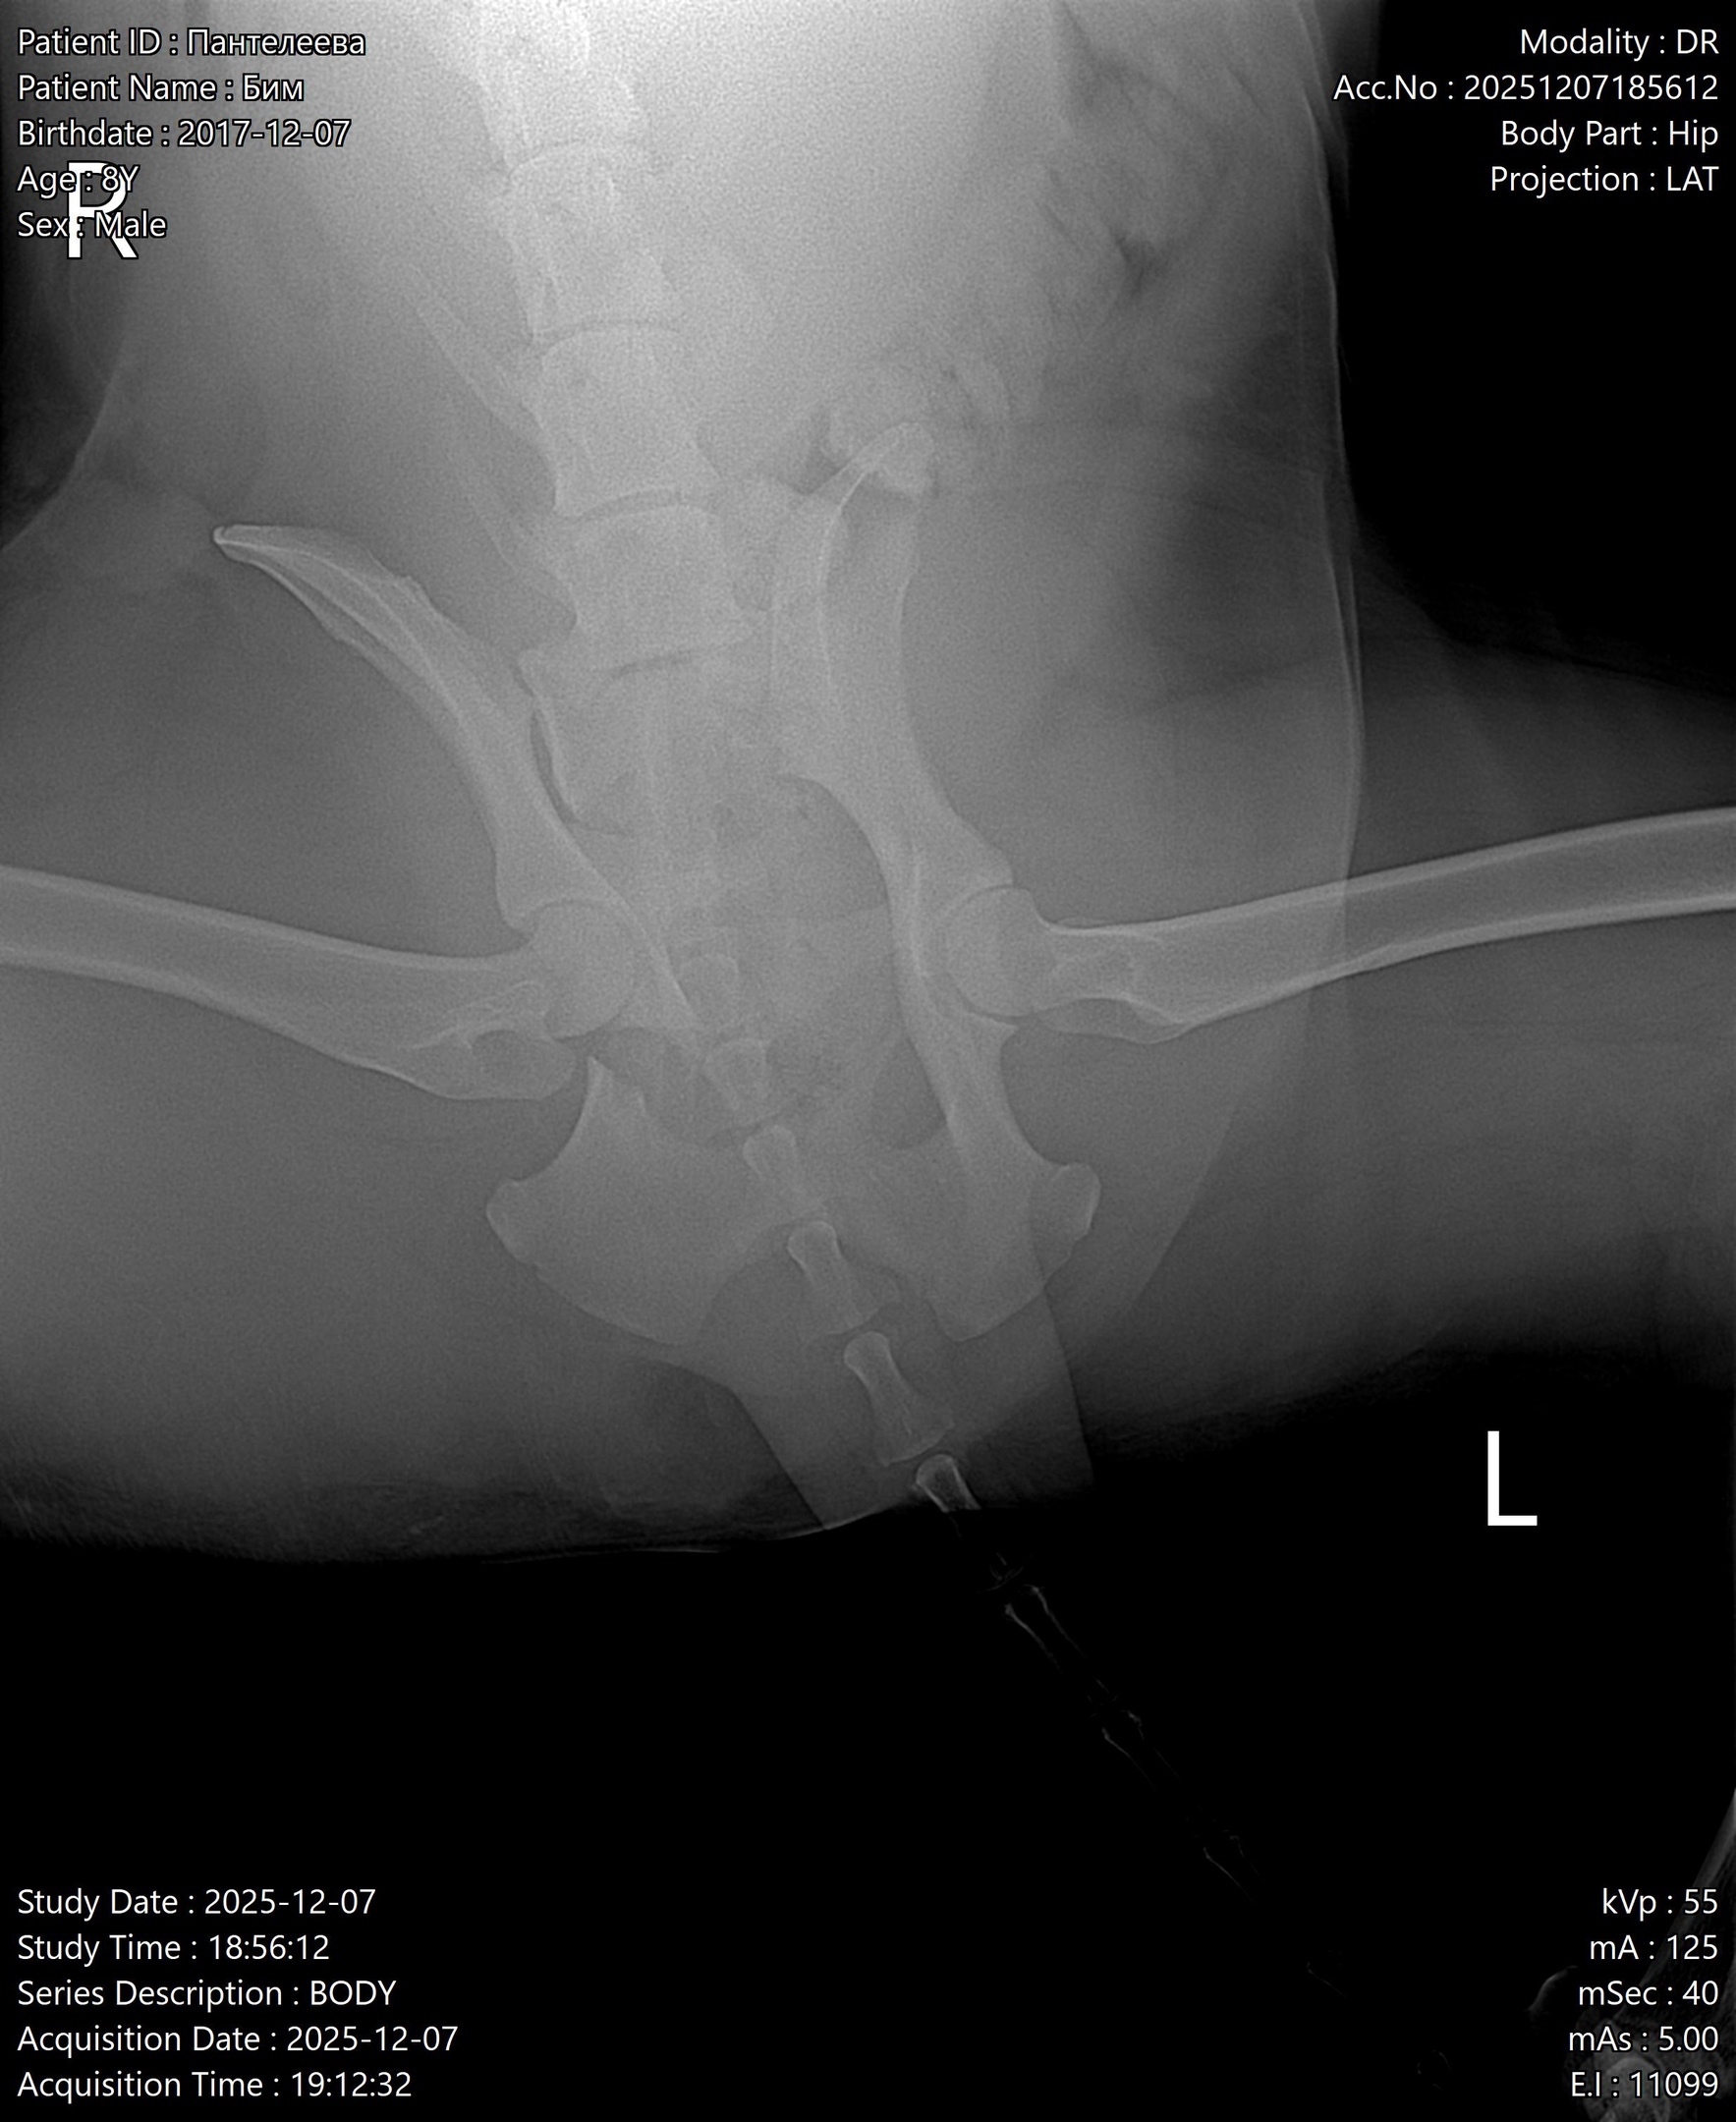

Недавно собачку (Бима ) Переехала «Газель »,ему очень сильно нужна помощь, видь его жизнь и так тяжелая у него нет дома и любящих хозяев.У собаки серьёзные травмы: (перелом таза ). Ветеринар сказал, что без операции он будет всю жизнь мучиться от боли в ноге и не факт, что вообще будет ходить😢